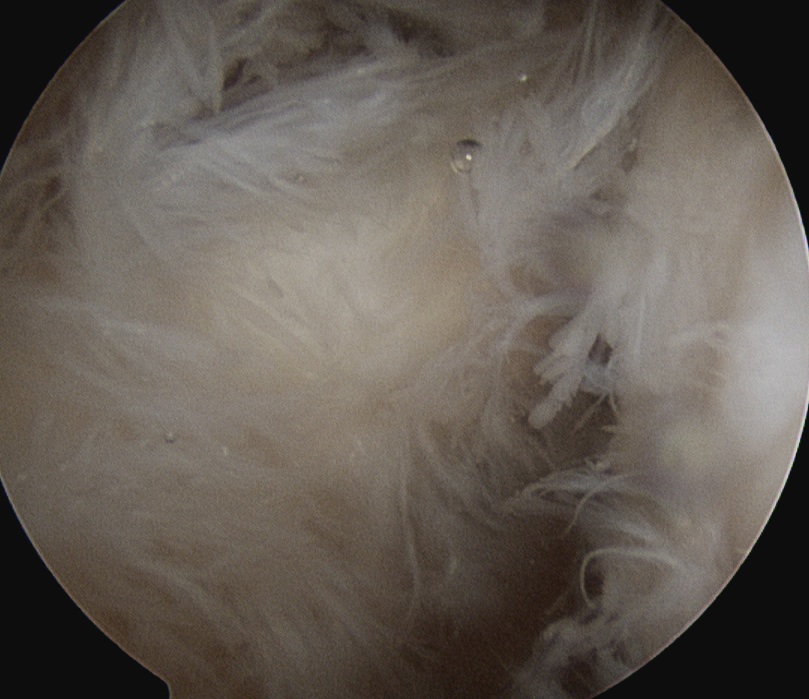

Arthroscopic Synovectomy

Kanbe et al. Eur J Orthop Surg Traumatol 2015

- arthroscopic synovectomy and capsular release for 54 RA shoulders

- mean follow up 5 years

- 67% receiving biologic treatments

- improvements in function and ROM